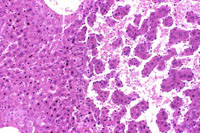

Dilated vascular spaces have replaced hepatic parenchyma in this hemangioma. High magnification shows dilated vascular spaces lined by flattened and sometimes dome-shaped endothelial cells and mild atrophy of the visible hepatic cords.

This hemangioma has isolated small clusters of hepatocytes; higher magnification shows proliferation of flattened endothelial cells.